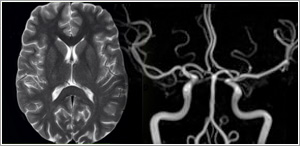

Neuro Imaging

MRI is considered the imaging modality of choice for most diseases affecting the central nervous system (brain and spine). Besides routine brain imaging, MRI is excellent at demonstrating diseases involving the internal auditory canals, pituitary gland, and orbits. Diffusion MRI is currently the earliest imaging modality for detecting acute stroke.

MR Angiography (MRA)

This technique uses flowing blood to obtain detailed images of the blood vessels. The examination is fast and easy to do, and produces images that approach the quality of traditional invasive catheter angiography.